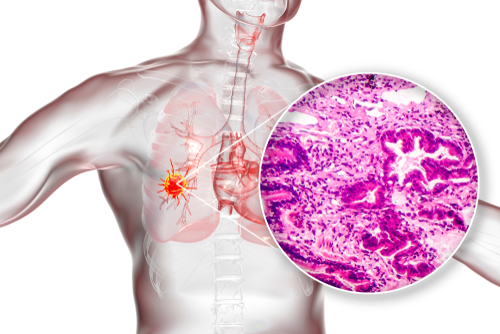

START domain-containing proteins (STARDs) are helpful prognostic and diagnostic biomarkers in patients with lung adenocarcinoma, specifically STARD12 and STARD14.

Recent study findings showed that STARD5/10/14 were overexpressed in lung adenocarcinoma compared with normal samples, while STARD4/7/8/11/12/13 were low. Moreover, STARD5/12/14 levels were positively related to clinical and lymph node stage.

Researchers, led by Wen-Di Zhang, determined that STARD12/14 have the greatest potential of being specific biomarkers of the disease. Of interest, high STARD12 expression was associated with better overall survival (OS), disease-specific survival (DSS), and disease-free survival (DFS). However, patients with STARD14 had significantly worse OS, DSS, and DFS.